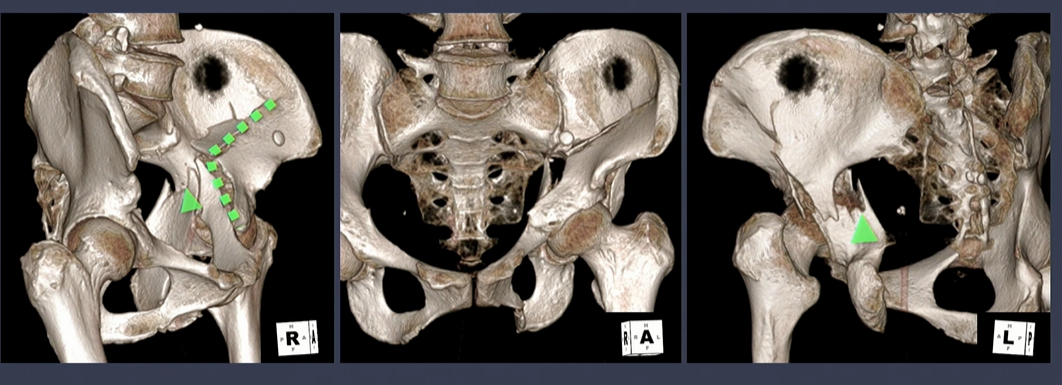

iliac wing쪽 골절선(녹색 점선)에 더해서, sciatic notch로 이어지는 골절선(녹색 화살표)을 확인.

노란색 별은 buttress 부위.

Spur sign은 both column fracture의 pathognomonic sign.